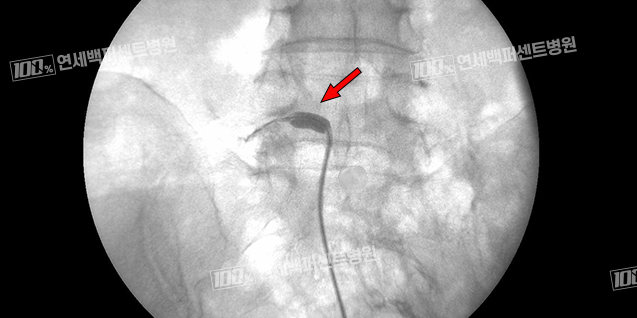

풍선 확장 경막외 신경성형술

꼬리뼈로 카테터를 삽입해 병변까지 도달시킨 뒤 카테터 끝에 달린 풍선을 확장해

협착부위를 넓히고 직접 염증 완화 및 유착방지 약물을 주입하는 시술입니다.

척추전방전위증

풍선확장술